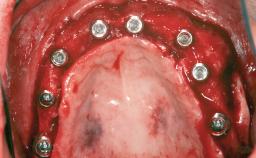

Ridge Preservation and Implant Placement for a Fixed Dental Prosthesis After a Car Accident

| # of Teeth | 6 |

| # of Implants | 4 |

| Type of Implants | One-Piece|Reduced-Diameter |

| Bone Augmentation | Horizontal|Simultaneous|Sinus Floor Elevation|Staged |

| Augmentation Materials | Xenogenous|Membrane |